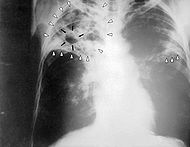

Chest X-ray - If a patient had a positive skin test response, the doctor would perform a chest X-ray. If it is just an infection then the X-ray would show white spots where the immune system has walled off the Tuberculosis bacteria. However if the patient has active TB it could show a nodule or large air space in the lungs.

Chest X ray diagnosing active TB. Image courtesy of en.wikipedia.org/wiki/File:Tuberculosis-x-ray-1.jpg. As work of the U.S. federal government this image is in the public domain and copyright free.